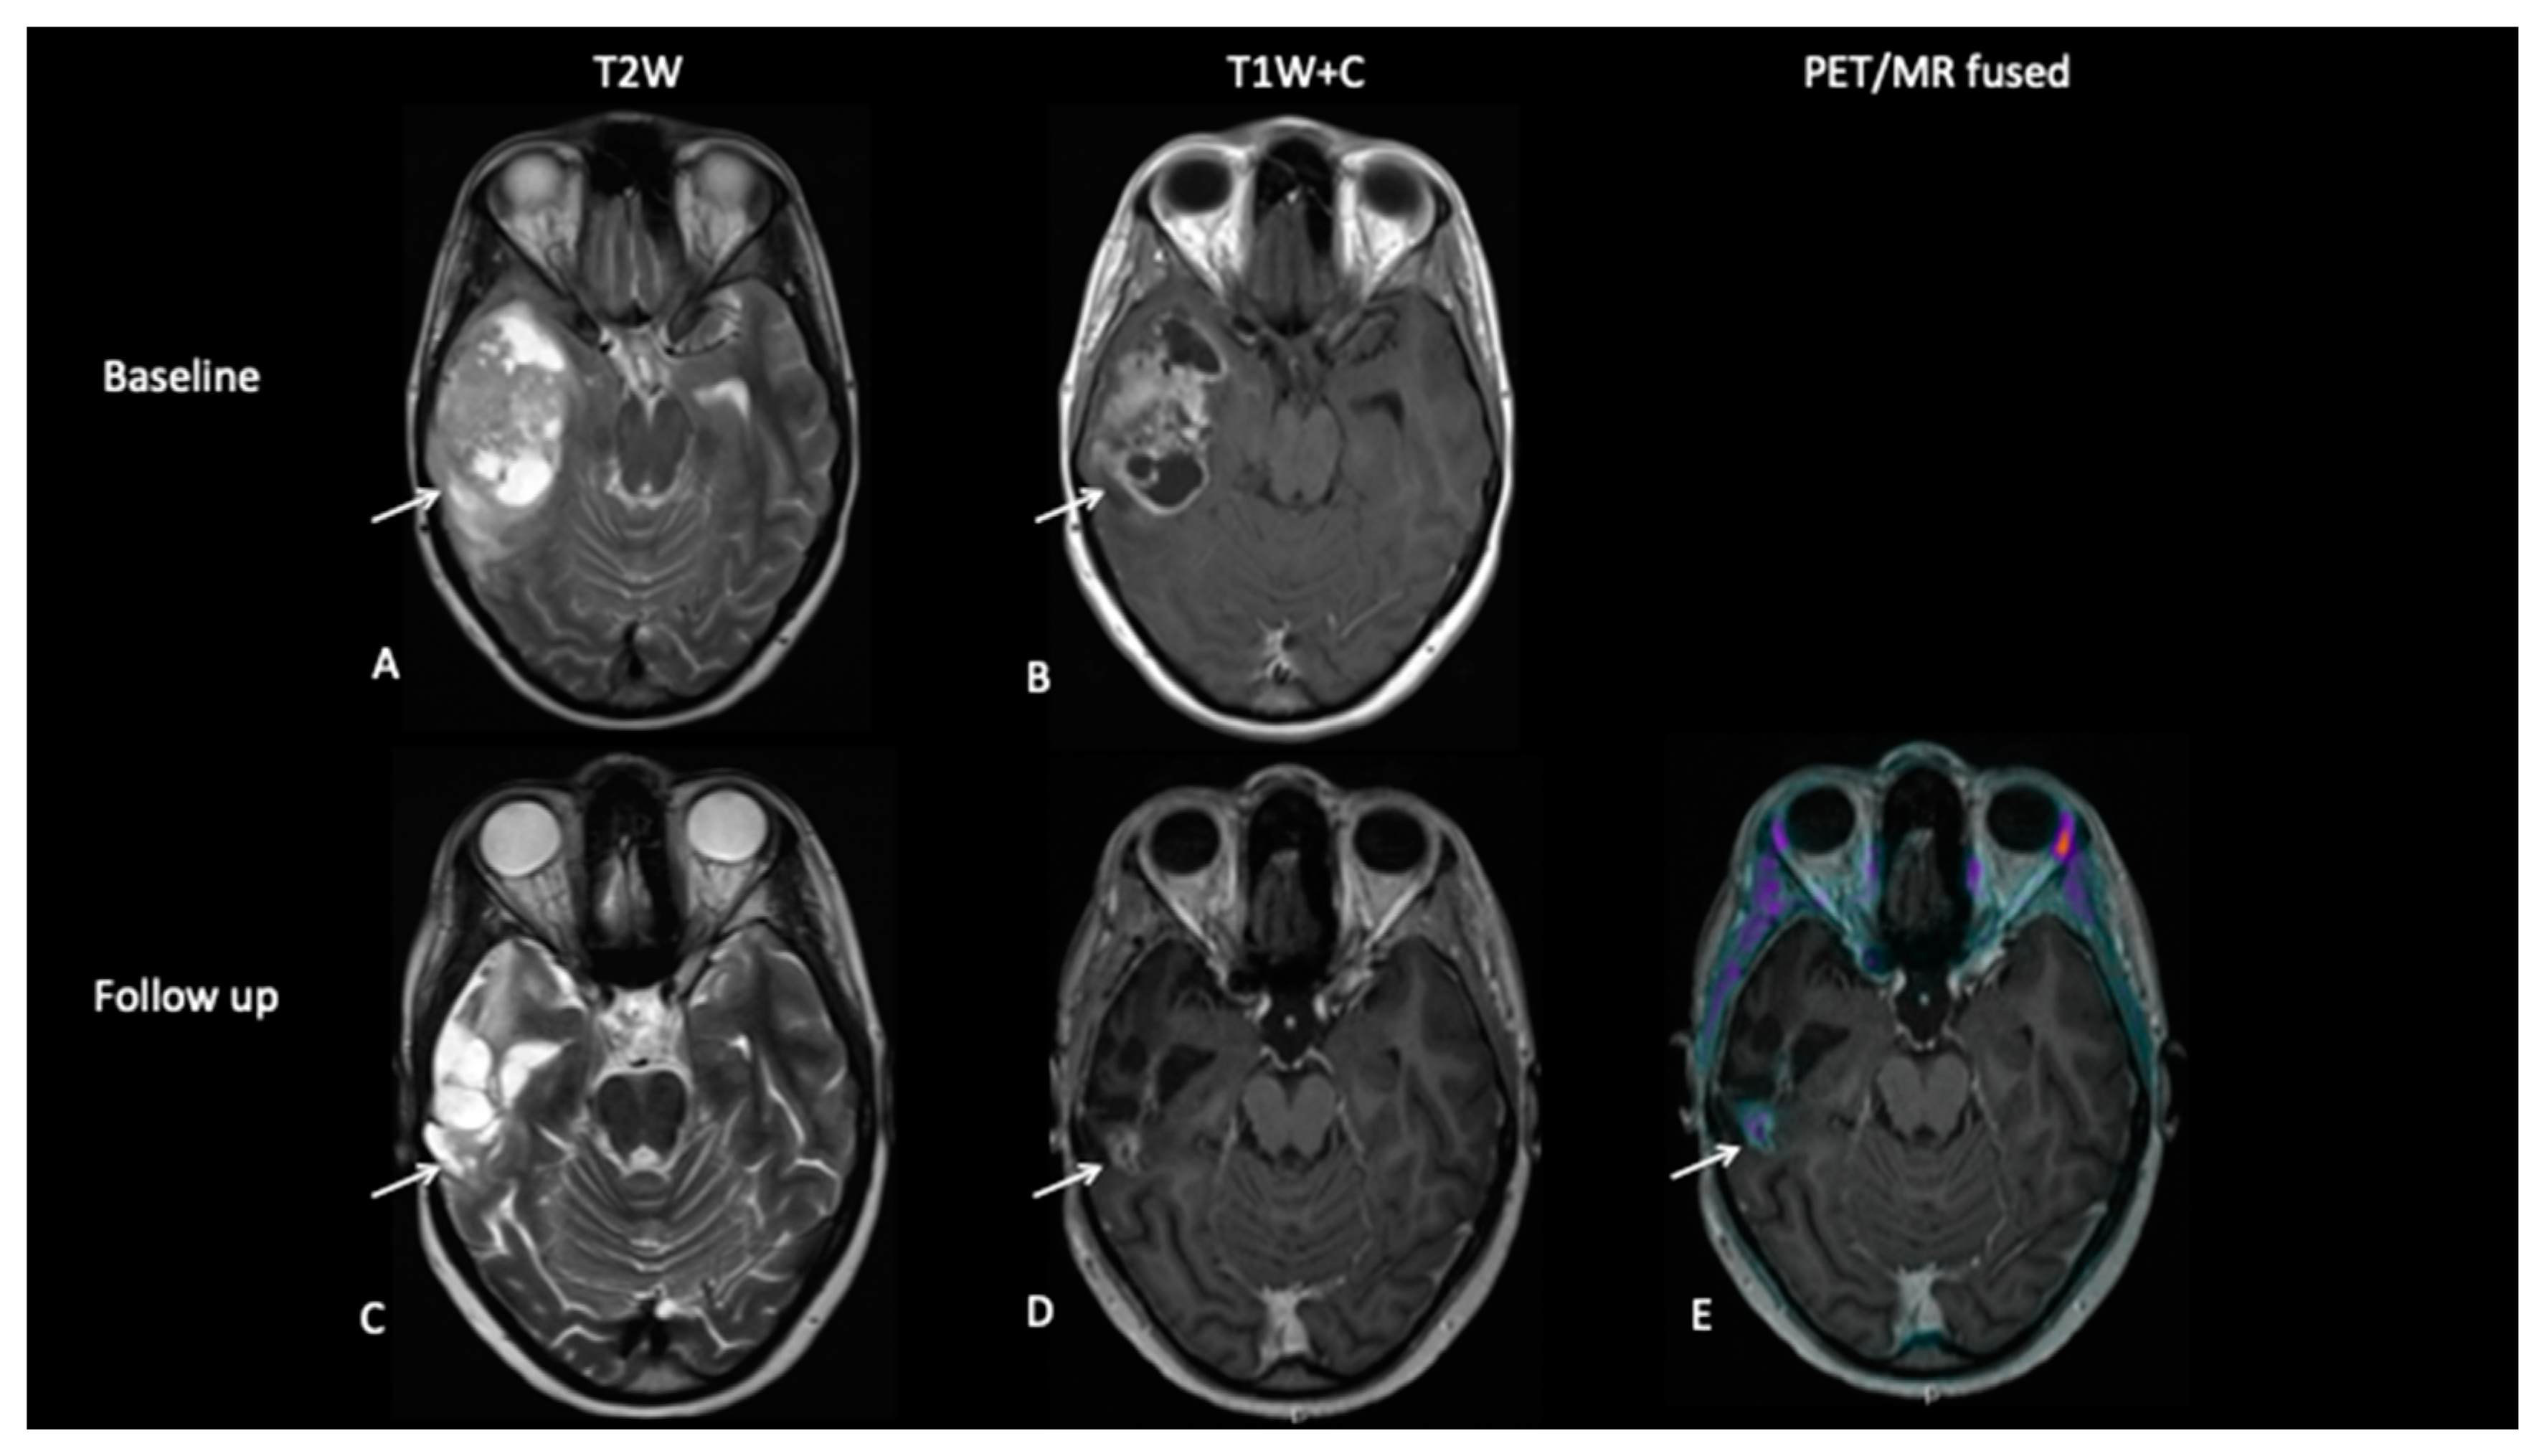

- Patient 5: End of Treatment Assessment

An 18-year-old female presented with a short history of headaches, vomiting and blurred vision. MRI scan at diagnosis (Figure 8) showed a large temporal lobe tumour. She underwent a sub-total resection and then commenced a 6-week course of chemoradiotherapy followed by 14 months of maintenance chemotherapy. Whilst the gadolinium contrast MRI scan at the end of treatment 18 months later demonstrated residual enhancement, FCho demonstrated no uptake, suggesting that the mass was non-viable.

Figure 8.

Baseline imaging demonstrates a large heterogenous right temporal lobe tumour (A) with avid enhancement (B). Follow-up imaging demonstrates the post-surgical resection on the T2W image (C) with nodular enhancement at the deep surgical margin (D), suspicious for residual tumour, but there is no increased uptake on FCho (E).